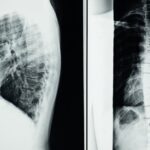

Quels examens permettent de diagnostiquer la sciatique?

Une IRM ou une radiographie est généralement nécessaire pour confirmer la cause de la sciatique.